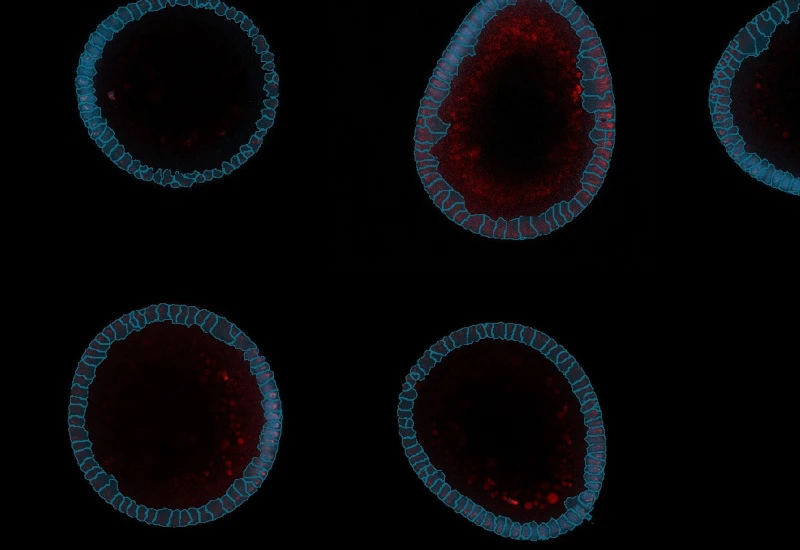

Analysis of Organoid and Immune Cell Co-Cultures By Machine Learning-powered Image Cytometry

The StrataQuest Organoid App provides reliable and efficient high-throughput validation and quantification for organoids co-cultured alongside immune cells.